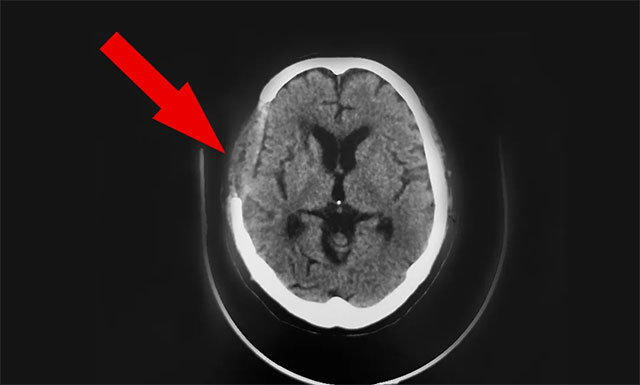

手术后一天,患者胡某苏醒,头脑清醒,并能下地走动。

▲ 手术后

10月8日,双节的最后一天,患者神志清,精神佳,眼球各向活动好,伸舌居中,张口、鼓腮、吹起动作可,双肺呼吸音清,四肢肌张力正常,双侧巴氏征未引出。基于患者恢复可,予以办理出院。